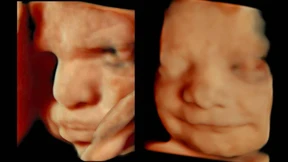

Was fühlt der Fötus, wenn er mürrisch blickt?

4D-Ultraschall ermöglicht inzwischen detailgetreue Abbildungen von ungeborenen Babys. Selbst ihre Gesichtsmimik wird in Echtzeit deutlich sichtbar. Aber bedeutet ein Lächeln wirklich Zufriedenheit, ein mürrisches Gesicht das Gegenteil?